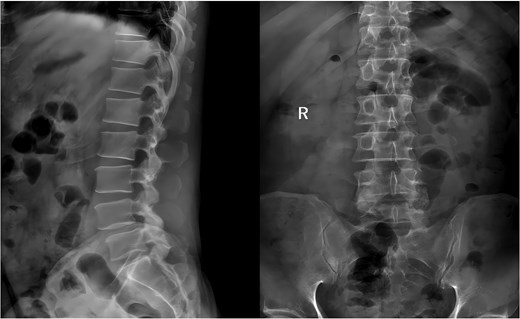

A 49-year-old male presented with a 10-month history of low back pain accompanied by numbness in the left lower limb. Over the past 2 weeks, his symptoms had progressively worsened without any identifiable precipitating factor, with increasing pain and numbness radiating down the left lower extremity. The patient reported that walking about 20 meters aggravated his symptoms, which were relieved after rest, allowing him to walk another short distance before the pain recurred. Due to the lack of significant relief from over-the-counter analgesics and topical medications, he presented to our outpatient clinic for further evaluation. Clinical examination and preoperative imaging demonstrated lumbar spinal stenosis at the L4/L5 level, lumbar instability, and grade I spondylolisthesis at L4 (Fig. 1). Following a comprehensive preoperative assessment, the patient was scheduled for PE-PLIF.

Preoperative anteroposterior and lateral radiographs of the lumbar spine.